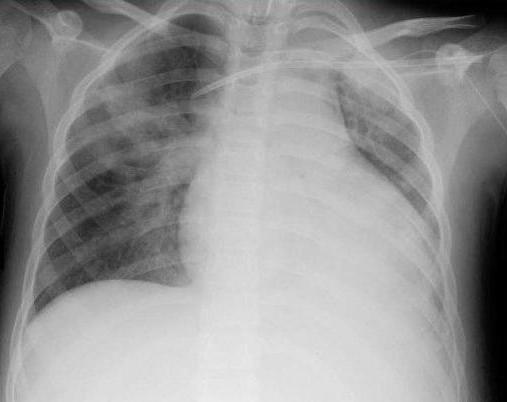

Если у человека появилась кровь изо рта, необходимо срочно вызвать скорую помощь. Для выявления причины данного симптома врач должен выяснить у родственников, какие заболевания или жалобы имелись у пациента ранее. При подозрении на кровотечение из пищеварительного тракта проводится ФГДС. Если источник повреждения находится в легких, в стационаре выполняют бронхоскопию. Также требуется рентгенография грудной клетки и брюшной полости. Для определения степени кровопотери проверяют уровень гемоглобина и эритроцитов. Также требуется коагулограмма. Она нужна для исключения патологий крови.